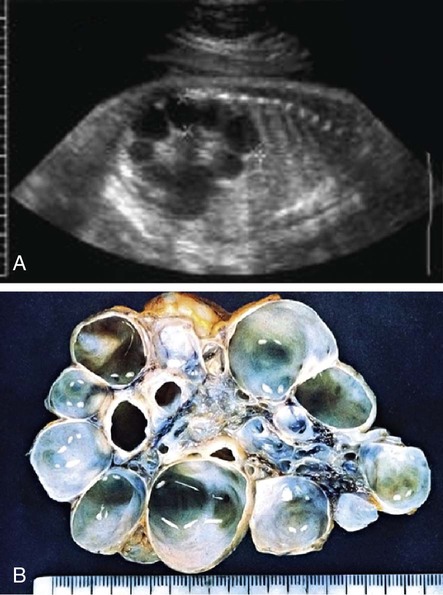

Renal dysgenesis refers to maldevelopment of the kidney that affects its size, shape, or structure. The 3 principal types of dysgenesis are dysplastic, hypoplastic, and cystic. Although dysplasia always is accompanied by a decreased number of nephrons (hypoplasia), the converse is not true: Hypoplasia can occur in isolation. When both conditions are present, the term hypodysplasia is preferred. The term dysplasia is technically a histologic diagnosis and refers to focal, diffuse, or segmentally arranged primitive structures, specifically primitive ductal structures, resulting from abnormal metanephric differentiation. Nonrenal elements, such as cartilage, also may be present. The condition can affect all or only part of the kidney. If cysts are present, the condition is termed cystic dysplasia. If the entire kidney is dysplastic with a preponderance of cysts, the kidney is referred to as a multicystic dysplastic kidney (MCDK) (Fig. 537-2).

MCDK is a congenital condition in which the kidney is replaced by cysts and does not function; it can result from ureteral atresia. Kidney size is highly variable. The incidence is approximately 1 in 2,000. Some clinicians incorrectly use the terms multicystic kidney and polycystic kidney interchangeably. However, polycystic kidney disease is an inherited disorder that may be autosomal recessive or autosomal dominant and affects both kidneys (see Chapter 521). MCDK usually is unilateral and generally is not inherited. Bilateral MCDKs are incompatible with life.

MCDK is the most common cause of an abdominal mass in the newborn, but the vast majority are nonpalpable at birth. In most cases, it is discovered incidentally during prenatal sonography. In some patients, the cysts are identified prenatally, but the cysts regress in utero and no kidney is identified on imaging at birth. Contralateral hydronephrosis is present in 5-10% of patients. Sonography shows the characteristic appearance of a kidney replaced by multiple cysts of varying sizes that do not communicate, and no identifiable parenchyma is present. In the past, most cases were confirmed with a renal scan, which should demonstrate nonfunction. However, presently the diagnosis of MCDK is usually straightforward based on the renal ultrasound, and a scan generally is unnecessary. In some patients, usually boys, a small nonobstructing ureterocele is present in the bladder (see Chapter 540). Although 15% have contralateral vesicoureteral reflux, it is usually low grade, and obtaining a voiding cystourethrogram also is unnecessary, unless there is significant contralateral hydronephrosis or the child develops an upper urinary tract infection. Management is controversial. Complete cyst regression occurs in nearly half of MCDKs by age 7 yr. The risk of associated hypertension is 0.2-1.2%, and the risk of Wilms tumor arising from an MCDK is approximately 1 in 1,200. Because neoplasms arise from the stromal rather than the cystic component, even if the cysts regress completely, the likelihood that the kidney could develop a neoplasm is not altered.